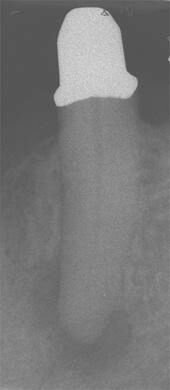

Gleicher Zahn kurz nach erfolgter Wurzelkanalbehandlung. -

Erfolgreich abgeheilte Entzündung 6 Monate später. Beschwerdefreier Zahn.